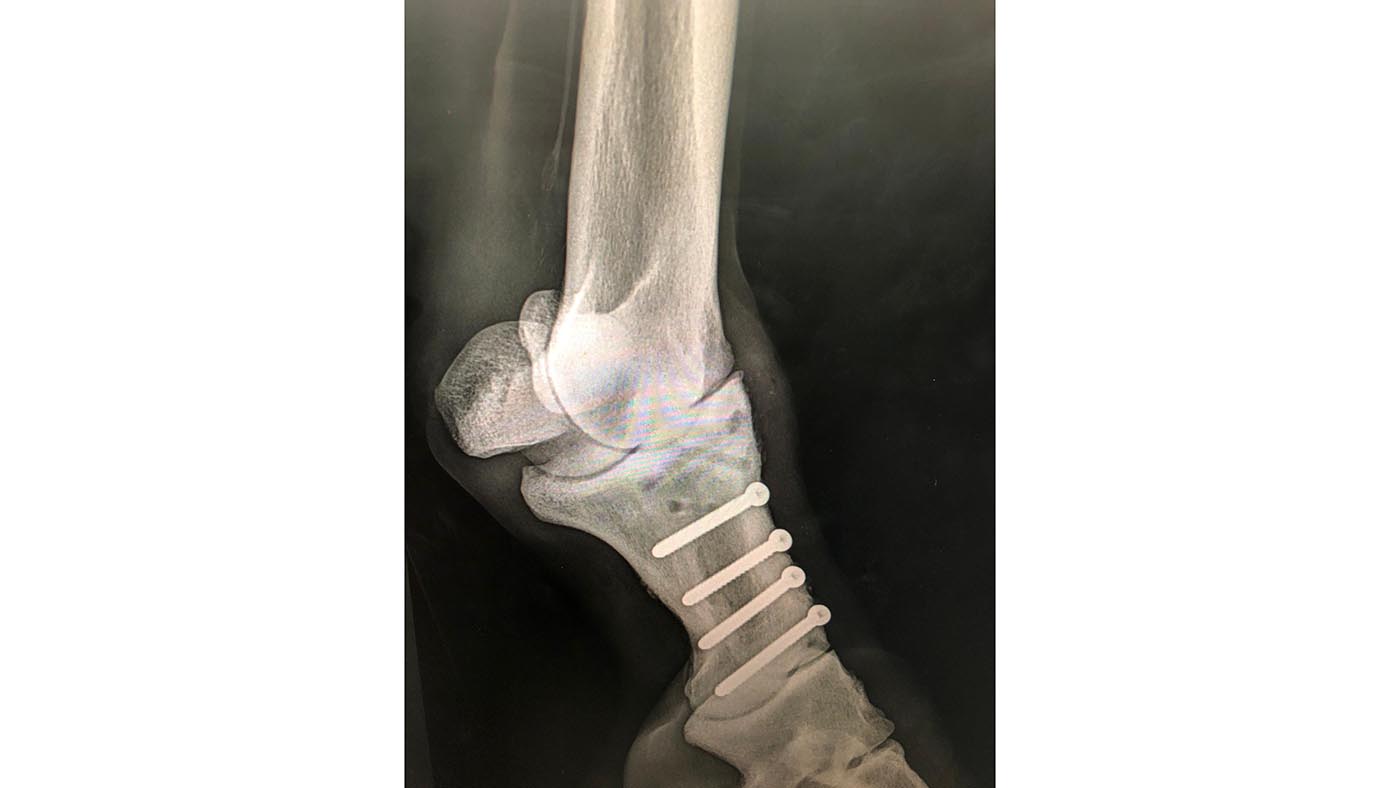

The much-loved chestnut was taken away in a horse ambulance and X-rays revealed a broken off-fore pastern, which was quickly operated on and put in a cast. The future looked uncertain.